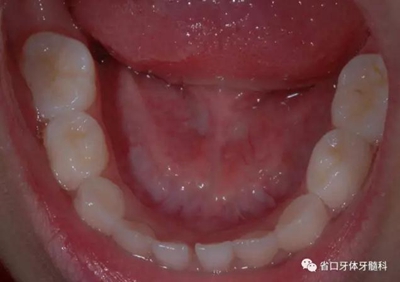

圖8 下頜牙相

9.jpg